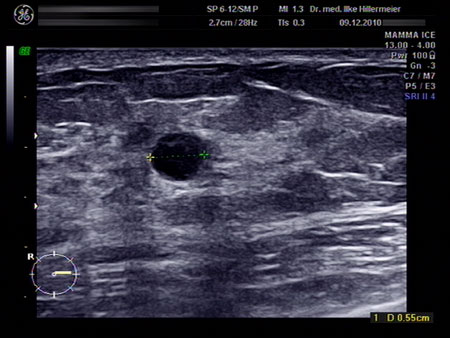

Frauenarztpraxis Dr Ilke Hillermeier